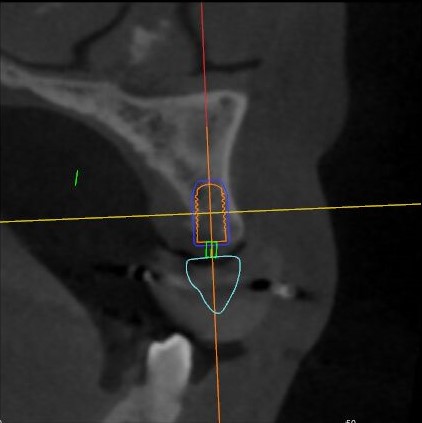

※實時導(dǎo)航:輕松把控種植位點、角度、深度,與術(shù)前CBCT整合顯示在一起,實時引導(dǎo)手術(shù)進(jìn)行,同時可以實現(xiàn)手術(shù)器械的可視化與實時跟蹤。

根據(jù)患者CT顯示,使用種植導(dǎo)航軟件設(shè)術(shù)前手術(shù)方案??紤]到患者拒絕手術(shù)摘除上頜竇囊腫等因素,此次手術(shù)選用了Straumann骨水平4.10*8.0mm的植體,植體末端位點設(shè)計距上頜竇底壁2mm處的同時兼顧種植方向和修復(fù)間隙,來達(dá)到理想的效果。

導(dǎo)航下精細(xì)分配修復(fù)間隙,精細(xì)規(guī)劃植入方向,避開上頜竇底,精確植入

從術(shù)后CBCT顯示可以看出,手術(shù)操作中完美地避開上頜竇底,并兼顧了正確的種植方向和修復(fù)間隙